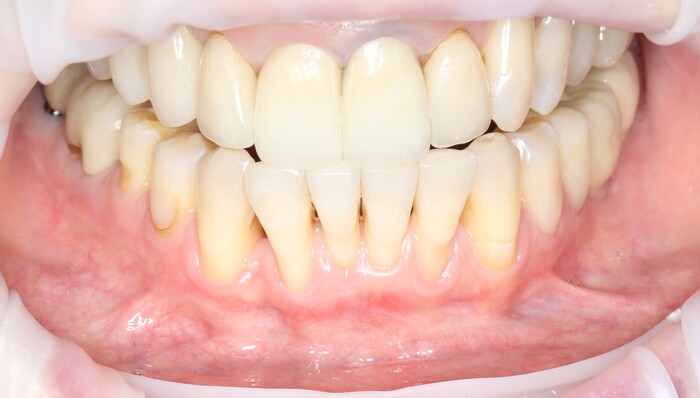

Еще через пару месяцев временную коронку сняли для изготовления новой:

И вот картинка спустя полгода «ношения» новой временной коронки: